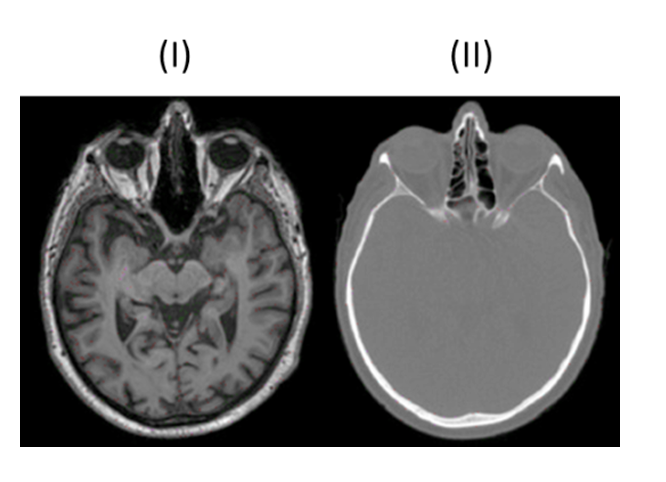

MRT (Bild I)

Strahlenfrei

hohe Bildqualität

Weichteildarstellung

Flexibilität bei Schnittführung

MRT (Bild I) typische Merkmale

Erzeugung Graustufenbildern basierend auf Anregung der Wasserstoffprotonen im Gewebe

T1-Wichtung: Hervorhebung fetthaltiger Strukturen → Knochen schwarz, Fettgewebe weiß

T2-Wichtung: Hervorhebung wasserhaltiger Strukturen → Liquor weiß, weiße Substanz dunkelgrau

CT (Bild II)

CT (Bild II) typische Merkmale

Weniger Kontrast bei Weichgewebe

Weiße Knochen